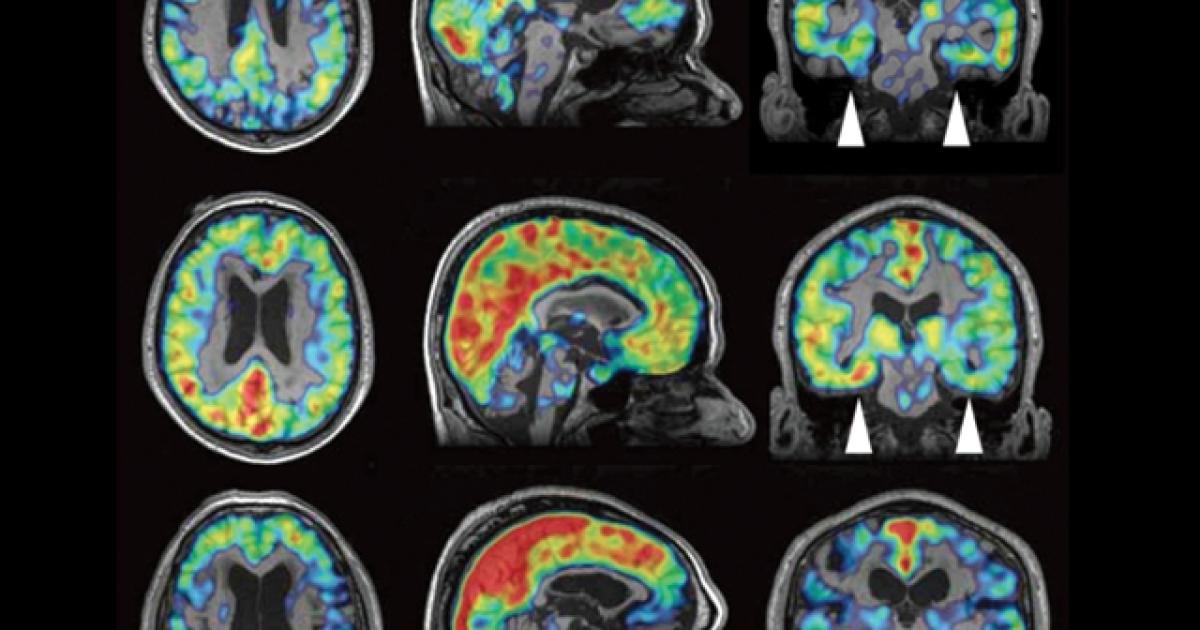

Radiology Brain Areas . brain mri with annotations of major structures. knowledge of the vascular territories is important, because it enables you to recognize infarctions in arterial. brain magnetic resonance imaging (mri) is a common medical imaging method that allows clinicians to examine the brain’s anatomy (1). Scroll through the images on the left. an understanding of brain arterial vascular territories is important in understanding stroke and complications. We also discuss the causes for their. it enables clinicians to focus on various parts of the brain and examine their anatomy and pathology, using different mri sequences,. radiology department, alrijne hospital leiden, the netherlands. in this article we describe 20 classic signs in neuroradiology and provide illustrations of each;

knowledge of the vascular territories is important, because it enables you to recognize infarctions in arterial. Scroll through the images on the left. We also discuss the causes for their. brain mri with annotations of major structures. an understanding of brain arterial vascular territories is important in understanding stroke and complications. in this article we describe 20 classic signs in neuroradiology and provide illustrations of each; brain magnetic resonance imaging (mri) is a common medical imaging method that allows clinicians to examine the brain’s anatomy (1). radiology department, alrijne hospital leiden, the netherlands. it enables clinicians to focus on various parts of the brain and examine their anatomy and pathology, using different mri sequences,.

Radiology Brain Areas brain magnetic resonance imaging (mri) is a common medical imaging method that allows clinicians to examine the brain’s anatomy (1). We also discuss the causes for their. in this article we describe 20 classic signs in neuroradiology and provide illustrations of each; radiology department, alrijne hospital leiden, the netherlands. it enables clinicians to focus on various parts of the brain and examine their anatomy and pathology, using different mri sequences,. knowledge of the vascular territories is important, because it enables you to recognize infarctions in arterial. brain magnetic resonance imaging (mri) is a common medical imaging method that allows clinicians to examine the brain’s anatomy (1). brain mri with annotations of major structures. Scroll through the images on the left. an understanding of brain arterial vascular territories is important in understanding stroke and complications.

Functional Brain Anatomy Radiology Key Radiology Brain Areas knowledge of the vascular territories is important, because it enables you to recognize infarctions in arterial. an understanding of brain arterial vascular territories is important in understanding stroke and complications. radiology department, alrijne hospital leiden, the netherlands. brain mri with annotations of major structures. brain magnetic resonance imaging (mri) is a common medical imaging method. Radiology Brain Areas.

Cerebral vascular territories Radiology Case Radiology Brain Areas brain mri with annotations of major structures. radiology department, alrijne hospital leiden, the netherlands. it enables clinicians to focus on various parts of the brain and examine their anatomy and pathology, using different mri sequences,. an understanding of brain arterial vascular territories is important in understanding stroke and complications. Scroll through the images on the left.. Radiology Brain Areas.

One step closer to invivo CTE diagnosis Radiology Brain Areas Scroll through the images on the left. brain magnetic resonance imaging (mri) is a common medical imaging method that allows clinicians to examine the brain’s anatomy (1). radiology department, alrijne hospital leiden, the netherlands. an understanding of brain arterial vascular territories is important in understanding stroke and complications. in this article we describe 20 classic signs. Radiology Brain Areas.